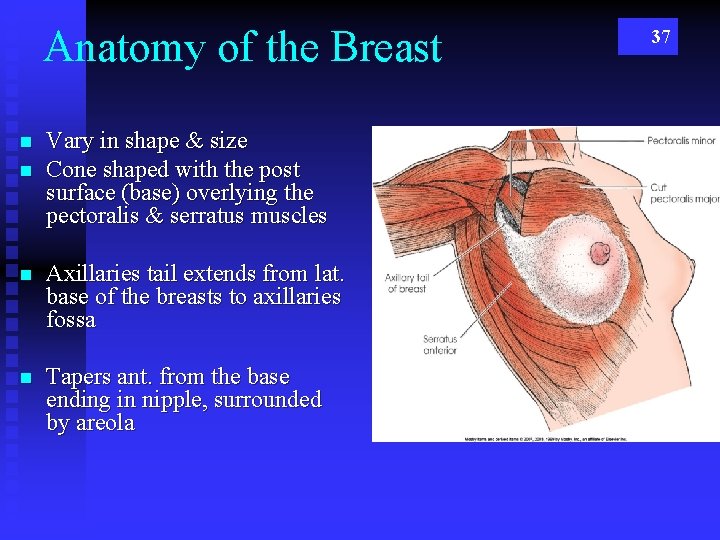

Anatomy of the Breast n n Vary in shape & size Cone shaped with the post surface (base) overlying the pectoralis & serratus muscles n Axillaries tail extends from lat. base of the breasts to axillaries fossa n Tapers ant. from the base ending in nipple, surrounded by areola 37